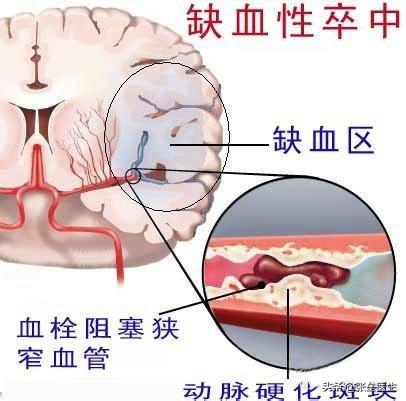

De nombreux ruraux ne reconnaissent pas l'infarctus cérébral. Qu'est-ce que l'infarctus cérébral ? L'infarctus cérébral est une maladie dans laquelle divers emboles sanguins (par exemple, un thrombus fixé à la paroi du cœur, une plaque d'athérosclérose, de la graisse, des cellules tumorales, du fibro-cartilage ou de l'air, etc.) pénètrent dans les artères cérébrales avec le flux sanguin et obstruent les vaisseaux sanguins, provoquant une nécrose ischémique des tissus cérébraux dans la zone desservie par les artères.

Pour simplifier, il s'agit de la nécrose des cellules cérébrales qui se produit lorsque les vaisseaux sanguins du cerveau sont bloqués, provoquant une ischémie cérébrale.

- Les AVC se divisent en AVC hémorragiques et en AVCaccident vasculaire cérébral ischémiqueIl existe deux catégories : la première est généralement appelée "hémorragie cérébrale" ou "hémorragie cérébrale", qui se manifeste généralement par des maux de tête intenses, des vomissements, voire le coma et d'autres symptômes ; la seconde est appelée "hémorragie cérébrale" ou "hémorragie cérébrale".La maladie de l'infarctus cérébral se réfère en fait à cette dernière。

- Infarctus cérébralÉgalement appelée "infarctus cérébral", "thrombose cérébrale" ou "embolie cérébrale", elle se manifeste généralement par l'apparition soudaine d'une faiblesse ou d'un engourdissement d'un côté des membres, d'un engourdissement d'un côté du visage ou d'une déformation des coins de la bouche, et d'un manque de réactivité, une perte d'équilibre, des difficultés à avaler, des difficultés à parler, des troubles de la conscience ou des convulsions.

L'infarctus cérébral, également connu sous le nom clinique d'accident vasculaire cérébral ischémique, est un problème d'approvisionnement en sang des vaisseaux sanguins du cerveau causé par un certain nombre de raisons telles que l'athérosclérose, l'hypertension, le diabète sucré et les maladies coronariennes, entraînant une ischémie, une hypoxie et une nécrose des tissus cérébraux locaux.

Les accidents vasculaires cérébraux peuvent être divisés en deux catégories : les accidents hémorragiques cérébraux et les accidents ischémiques cérébraux. L'accident vasculaire cérébral ischémique (infarctus cérébral) est le type d'accident vasculaire cérébral le plus courant en Chine.L'accident vasculaire cérébral ischémique est un état dans lequel le flux sanguin vers le cerveau est insuffisant en raison de l'obstruction des vaisseaux sanguins, ce qui entraîne une nécrose ischémique et une perte de fonction des tissus cérébraux, l'embolie cérébrale et la thrombose cérébrale étant les causes les plus courantes. Avant l'apparition de l'AVC ischémique, les patients peuvent présenter des symptômes temporaires d'ischémie cérébrale (communément appelés mini-AVC), notamment l'apparition soudaine d'un engourdissement et d'une faiblesse unilatérale des bras et des jambes, des troubles de l'élocution, une vision floue, une perte d'équilibre, etc.Il s'agit d'un précurseur important de l'accident vasculaire cérébral... Les plaques d'athérome et la sténose des artères carotides cérébrales sont des facteurs importants de l'accident vasculaire cérébral ischémique.Outre les personnes d'âge moyen et les personnes âgées, les patients souffrant d'hypertension artérielle, d'hypercholestérolémie, de diabète sucré et les fumeurs de longue date constituent également les groupes les plus fréquents.

- Thrombose cérébrale :(1) Formation de caillots sanguins en raison de l'augmentation de la viscosité du sang. (2) Obstruction de la circulation sanguine due à l'accumulation de graisse dans les artères du cerveau, qui forme une plaque et aggrave le rétrécissement des vaisseaux sanguins dans le cerveau.

- embolie cérébraleLes obstructions provenant d'autres parties du corps que le cerveau, telles que les caillots sanguins, la graisse, les bulles d'air, etc., pénètrent dans les vaisseaux sanguins cérébraux via le système circulatoire et provoquent une perturbation localisée de la circulation sanguine cérébrale.

L'infarctus cérébral est principalement causé par la concentration de lipides sanguins dans l'organisme, la formation de caillots sanguins dans les vaisseaux sanguins et le blocage de la circulation sanguine entraînant un infarctus cérébral, l'infarctus cérébral n'est pas au point de causer la mort, mais il y aura une hémiplégie, ou une paralysie, ou même deviendra végétatif, principalement en raison de la compression des nerfs du cerveau causée par la personne.